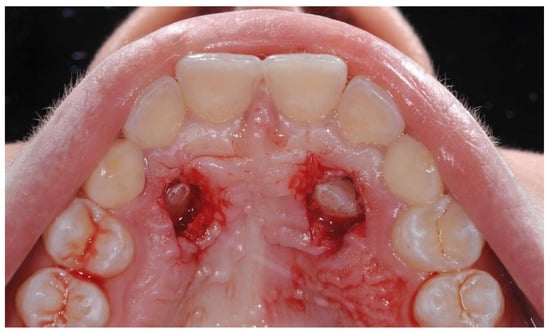

After collecting the initial documentation, the patient underwent the surgical procedure. Initially, local anesthesia was performed with 2% mepivacaine and 1:100,000 adrenaline solution. Subsequently, a cold blade was used to perform the operculectomy on the elements 1.3 and 2.3. This technique exposes the crown of the impacted teeth by cutting the tissue surface and then raising the palatal mucosa using a periosteal elevator. Afterwards, the osteotomy is performed using a handpiece with an ISO 018 diameter rosette bur (Maillefer®, Ballaigues, Switzerland), and simultaneously, abundant saline solution irrigates the spot to prevent the tissues from overheating. The crown of the canines was progressively uncovered by directing the drill tangentially along the bone surface (Figure 4).

Once the surgical procedure was completed, element 2.3, exposed on the palatal surface, was stimulated through PBMT, and finally a periodontal compress (Coe-Pak, GC Dental, Tokyo, Japan) was applied to cover and protect the treated area. No orthodontic anchoring and traction were placed on the canines’ exposed surfaces.

Figure 4. Intraoral occlusal photo of the patient after operculectomy with cold blade.